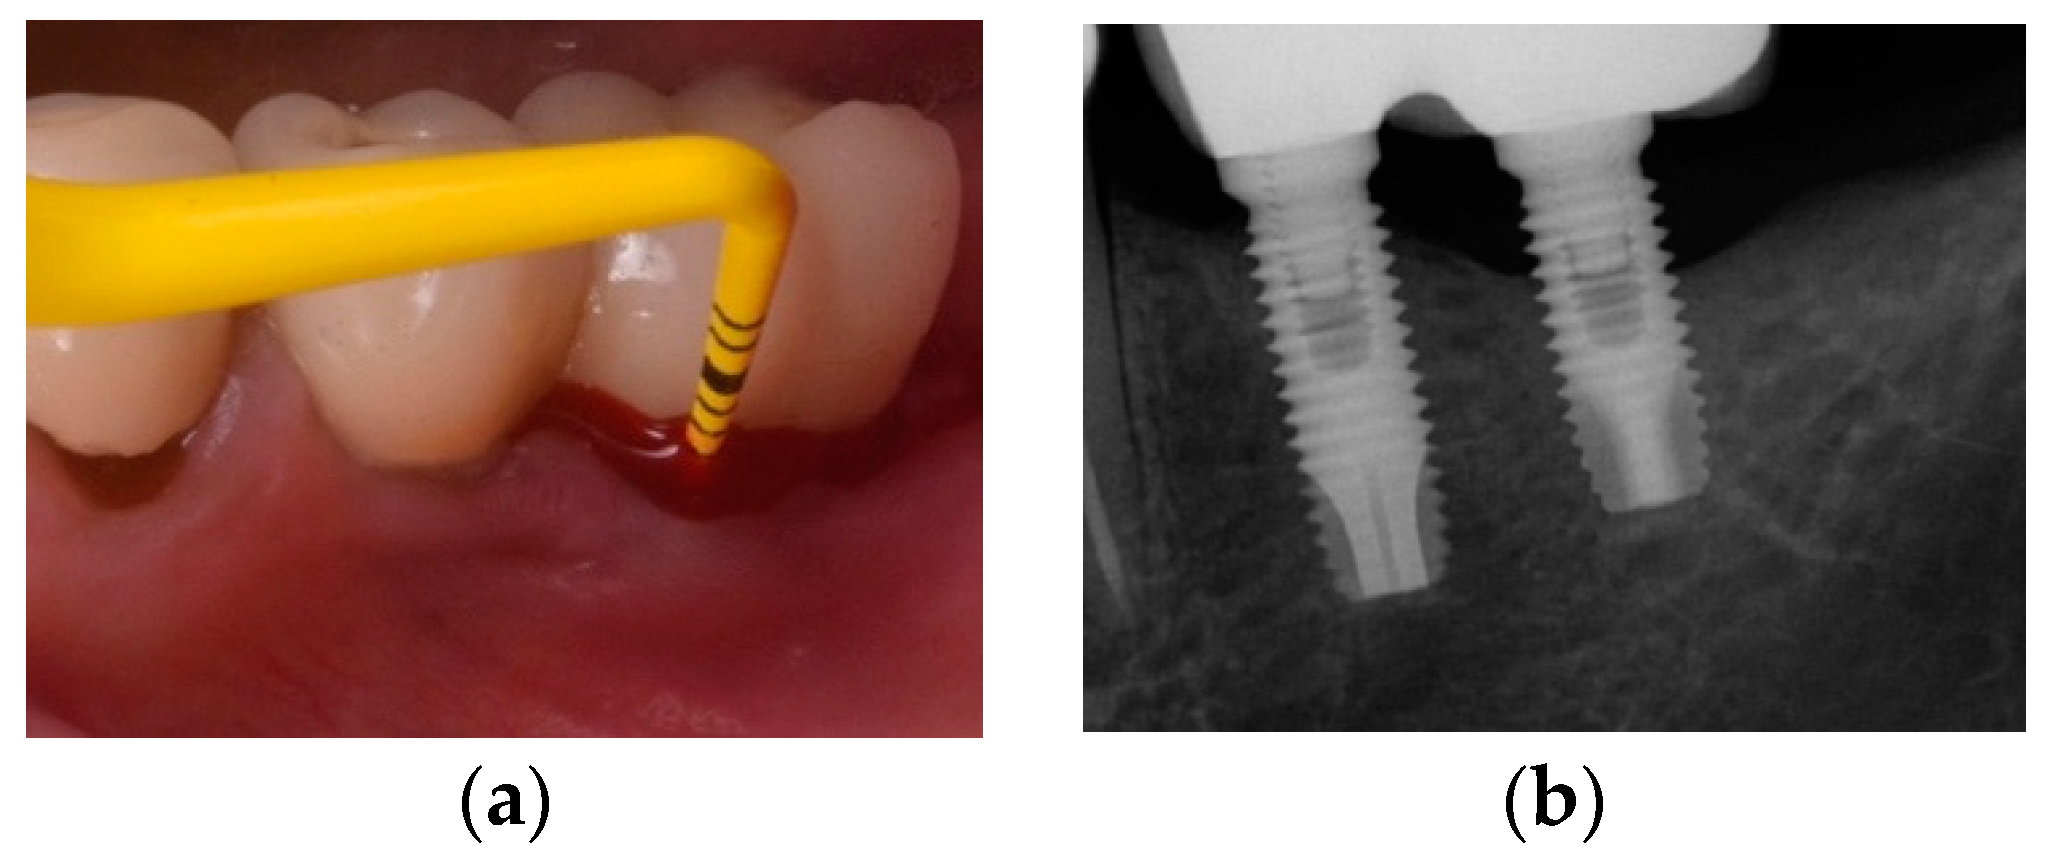

- Monje, A.; Blasi, G. Significance of keratinized mucosa/gingiva on peri-implant and adjacent periodontal conditions in erratic maintenance compliers. J. Periodontol. 2019, 5, 445–453. [Google Scholar] [CrossRef] [PubMed]

- Ravidà, A.; Saleh, I.; Siqueira, R.; Garaicoa-Pazmiño, C.; Saleh, M.H.A.; Monje, A.; Wang, H.L. Influence of keratinized mucosa on the surgical therapeutical outcomes of peri-implantitis. J. Clin. Periodontol. 2020, 4, 529–539. [Google Scholar] [CrossRef] [PubMed]

- Monje, A.; Blasi, G.; Nart, J.; Urban, I.A.; Nevins, M.; Wang, H.L. Soft Tissue Conditioning for the Surgical Therapy of Peri-implantitis: A Prospective 12-Month Study. Int. J. Periodont. Restor. Dent. 2020, 6, 899–906. [Google Scholar] [CrossRef] [PubMed]